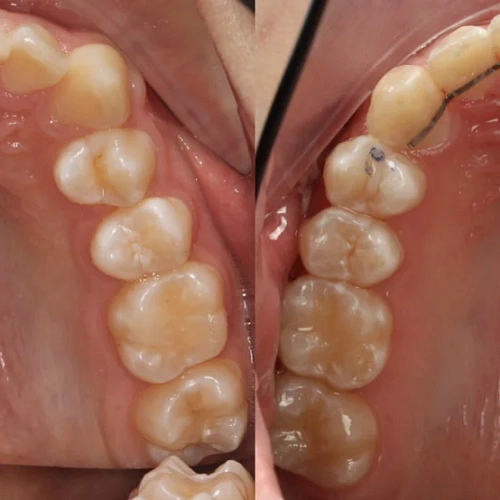

Зубы выровнены, смыкание нормализовано. Установлены несъёмные ретейнеры на обе челюсти. Пациент направлен к ортопеду.

Решение: Поставили элайнеры Invisalign на обе челюсти. Лечение заняло 4 года — случай потребовал нескольких этапов коррекции, каждый из которых последовательно приближал зубы к нужному положению. Капы менялись каждые 1–2 недели, контрольные визиты — для отслеживания прогресса и выдачи новых наборов. Зубы встали на место, смыкание пришло в норму. Зафиксировали ретейнеры на обе челюсти, пациент направлен к ортопеду для завершающего этапа.

Случай потребовал нескольких последовательных этапов коррекции. Invisalign позволяет дозаказывать капы в рамках лечения, и здесь это понадобилось — каждый следующий этап доводил положение зубов точнее. Результат достигнут, прикус стабилен, ретейнеры на месте. Пациента направила к ортопеду.